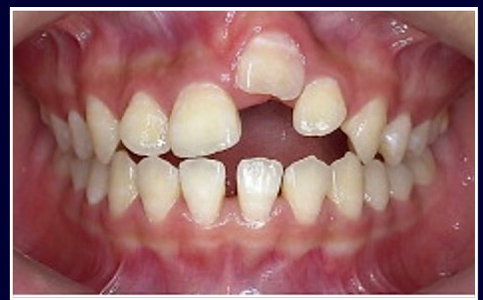

intrusive luxation

-can crush neurovascular bundle

-wait ~2-3 weeks to re-erupt

-get ortho consult right away in case re-eruption does not occur

intrusive luxation on primary teeth

-CBCT useful

-if no imminent damage to permanent tooth germ, wait 2-6 months to erupt

-if tooth germ damaged, must extract tooth